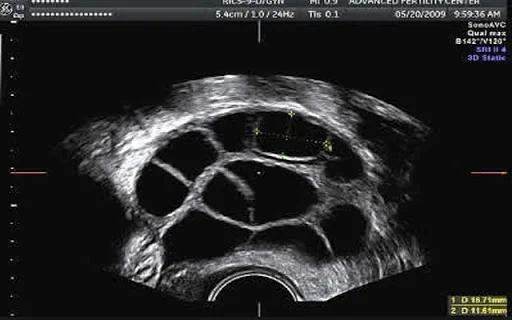

Яичник во время стимуляции выглядит примерно так:

Стимуляция занимает в среднем 10 дней. В конце ставится финальный укол, который приводит к созреванию ооцитов (яйцеклеток) и через 35-37 часов нужно провести пункцию.